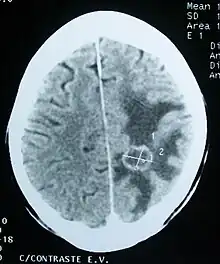

Imaging

Medical imaging plays a central role in the diagnosis of brain tumors. Early imaging methods – invasive and sometimes dangerous – such as pneumoencephalography and cerebral angiography have been replaced by non-invasive, high-resolution techniques, especially magnetic resonance imaging (MRI) and computed tomography (CT) scans.[42] MRI with contrast enhancement is the preferred imaging test in the diagnosis of brain tumors.[24][43] Glioblastomas usually enhance with contrast on T1 MRI weighted MRI imaging, and on T2 with FLAIR imaging showing hyperintense cerebral edema.[24] Low grade gliomas are usually hypointense on T1 MRI, and hyperintense with T2 with FLAIR MRI. Meningiomas are usually homogenously enhanced with dural thickening on MRI.[24]

Computed Tomography (CT) Scan – uses x-rays to take pictures from different angles and computer processing to combine the pictures into a 3D image. A CT scan usually serves as an alternative to MRI in cases where the patient cannot have an MRI due to claustrophobia or pacemaker. Compared to MRI, a CT scan shows a more detailed image of the bone structures near the tumor and can be used to measure the tumor's size.[51] Like an MRI, a contrast dye may also be injected into the veins or ingested by mouth before a CT scan to better outline any tumors that may be present. CT scans use contrast materials that are iodine-based and barium sulfate compounds. The downside of using CT scans as opposed to MRI is that some brain tumors do not show up well on CT scans because some intra-axial masses are faint and resemble normal brain tissue. In some scenarios, brain tumors in CT scans may be mistaken for infarction, infection, and demyelination. To suspect that an intra-axial mass is a brain tumor instead of other possibilities, there must be unexplained calcifications in the brain, preservation of the cortex, and disproportionate mass effect.[52]